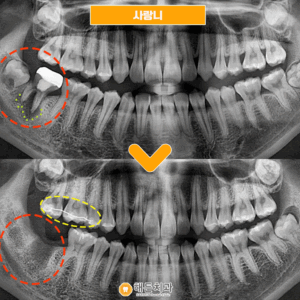

오늘 소개해 드릴 분께서는

오른쪽 아래 사랑니가 불편하셔서

본원을 찾아주셨는데요.

사랑니가 잇몸뼈를 뚫고 나오지 못해

매복되어 있는 상태를 확인할 수 있었으며

주변 잇몸이 자주 붓고 불편하셔서

발치하시길 원하셨습니다.

저희 해든치과에서는

발치 전 CT 촬영을 통해

사랑니의 위치, 신경과의 거리,

인접 구조물과의 거리 등

정밀하고 꼼꼼하게 체크 후에

안정적인 발치를 진행하였습니다.

발치가 깔끔하고

깨끗하게 마무리된 모습입니다.

♥ 치료 전/후 ♥

(2023.10.12 ㅡ> 2024.2.23)